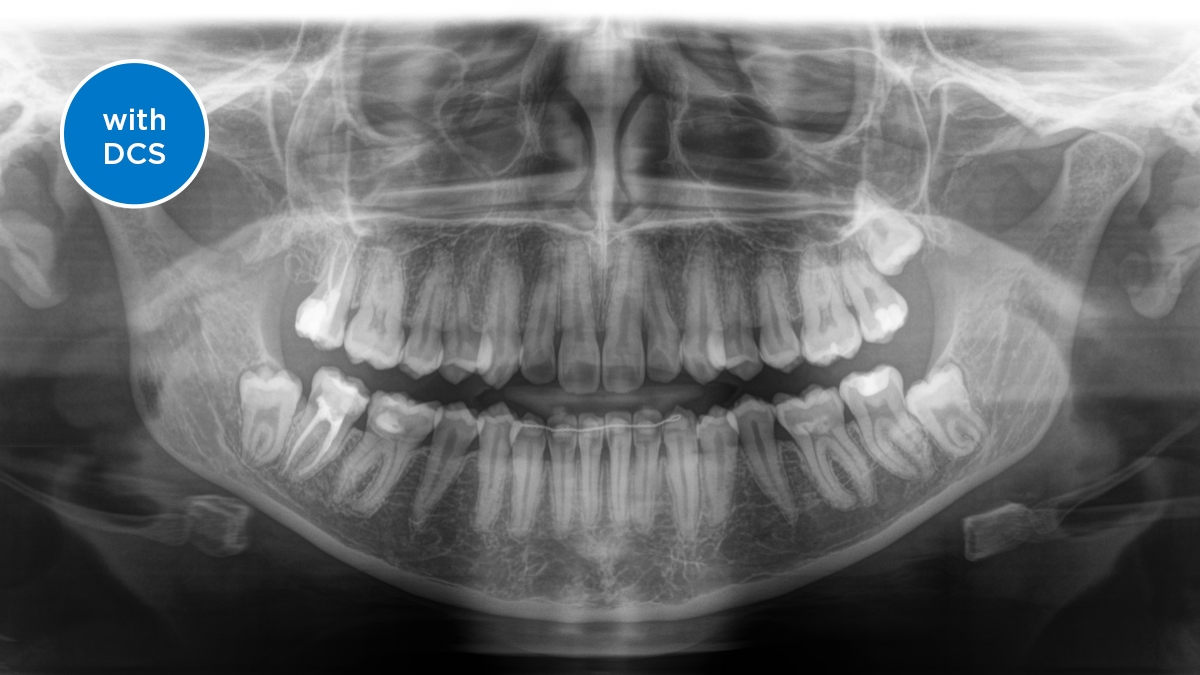

DCS converts X-rays directly into electrical signals, with no information loss. The DCS sensor creates razor-sharp, high-contrast panoramic X-ray images of exceptional quality.

Direct Conversion Sensor (DCS): Sharp Image Details

The Direct Conversion Sensor (DCS) has revolutionized the standard of panoramic imaging. X-rays are directly converted into electrical signals. Thus, there is no signal loss due to light conversion as with conventional systems. The result: images with an extremely high and high-contrast level of sharpness - even at a very low dose. For clear diagnoses and even more targeted treatment.

The image shows an X-ray image with and without DCS technology. Move the control over the image and see for yourself the difference the DCS sensor makes to the image quality.